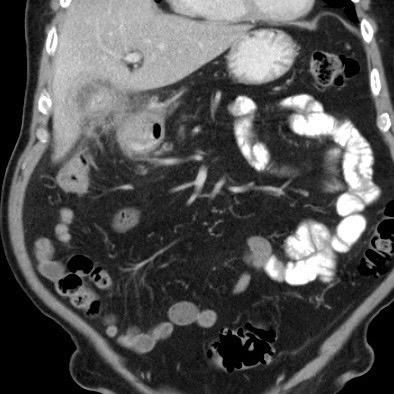

Hình ảnh của một bệnh nhân nữ cao tuổi, nhập viện vì ứ đọng dạ dày và nôn mửa.

CRP là 55, nhưng được ghi nhận là 160 vài ngày trước đó.

Siêu âm cho thấy một viên sỏi lớn trong túi mật chứa đầy chất lắng cặn, thành túi mật không đều.

Dạ dày giãn to và có dày thành tá tràng đáng kể (đầu mũi tên) kèm viêm xung quanh (dấu hoa thị).

Nội soi dạ dày được thực hiện do nghi ngờ ác tính, nhưng sinh thiết chỉ cho thấy hình ảnh viêm.

Tiếp tục xem CT.

CT xác nhận chẩn đoán hội chứng Bouveret.

Dẫn lưu túi mật qua da đã giải quyết các triệu chứng ứ đọng dạ dày.

Một năm sau, viên sỏi dường như đã tự di chuyển vào lòng tá tràng, và bệnh nhân phát triển tắc ruột do sỏi mật điển hình, được phẫu thuật thành công.